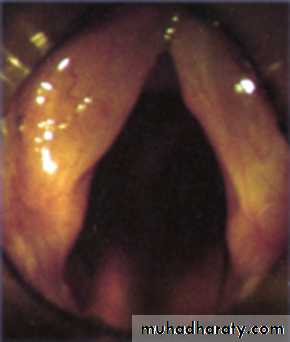

• Abductor paralysis:

• unilateral or bilateral.

Bilateral Abductor Paralysis

Position: Both cords lie near the midline (paramedian).Aetiology: It is most often caused by

Clinically: the quality of voice is good but sooner or later every patient will have stridor.